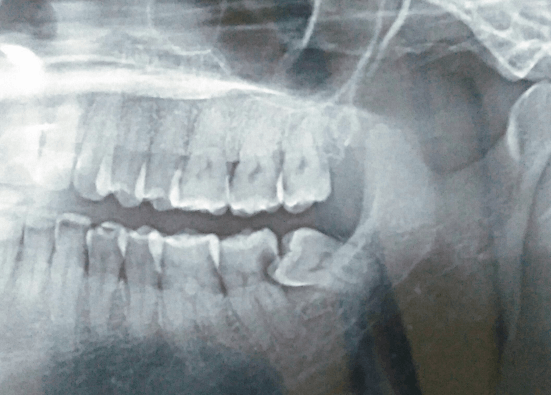

Inilah pertumbuhan gigi bungsu yang bermasalah yang tentunya jika hal tersebut tidak segera ditangani akan menimbulkan masalah lainnya yang lebih membahayakan, pada kasus yang terburuk gigi bungsu yang tumbuh tidak baik dapat menyebabkan terjadinya tumor atau kista pada gusi. Jika sudah pada masalah terburuk tersebut sudah seharusnya segera ditangani. Masalah yang diakibatkan dari tumbuhnya gigi bungsu yang tidak baik tentunya akan mengganggu fungsi gigi seperti terganggu dalam mengunyah makanan dan juga rasa nyeri yang muncul tersebut dapat membuat kesulitan dalam membersihkan rongga mulut. Kemunculan gigi bungsu yang bermasalah ini harus segera diatasi agar tidak menimbulkan masalah yang lebih serius lainnya, dalam menangani kondisi seperti ini dapat dilakukan dengan operasi gigi.